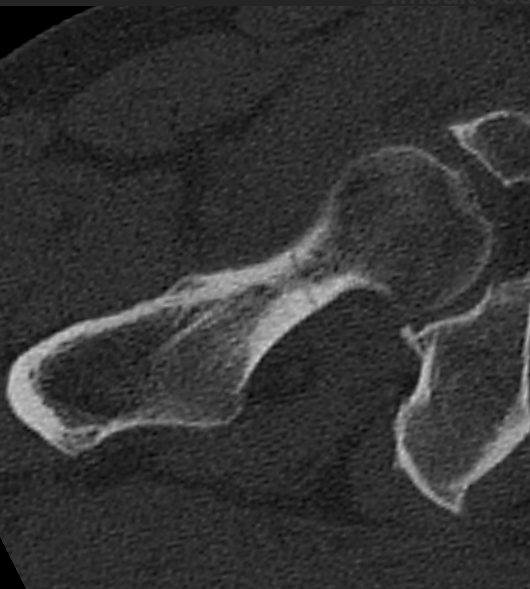

3. Occult hip fracture